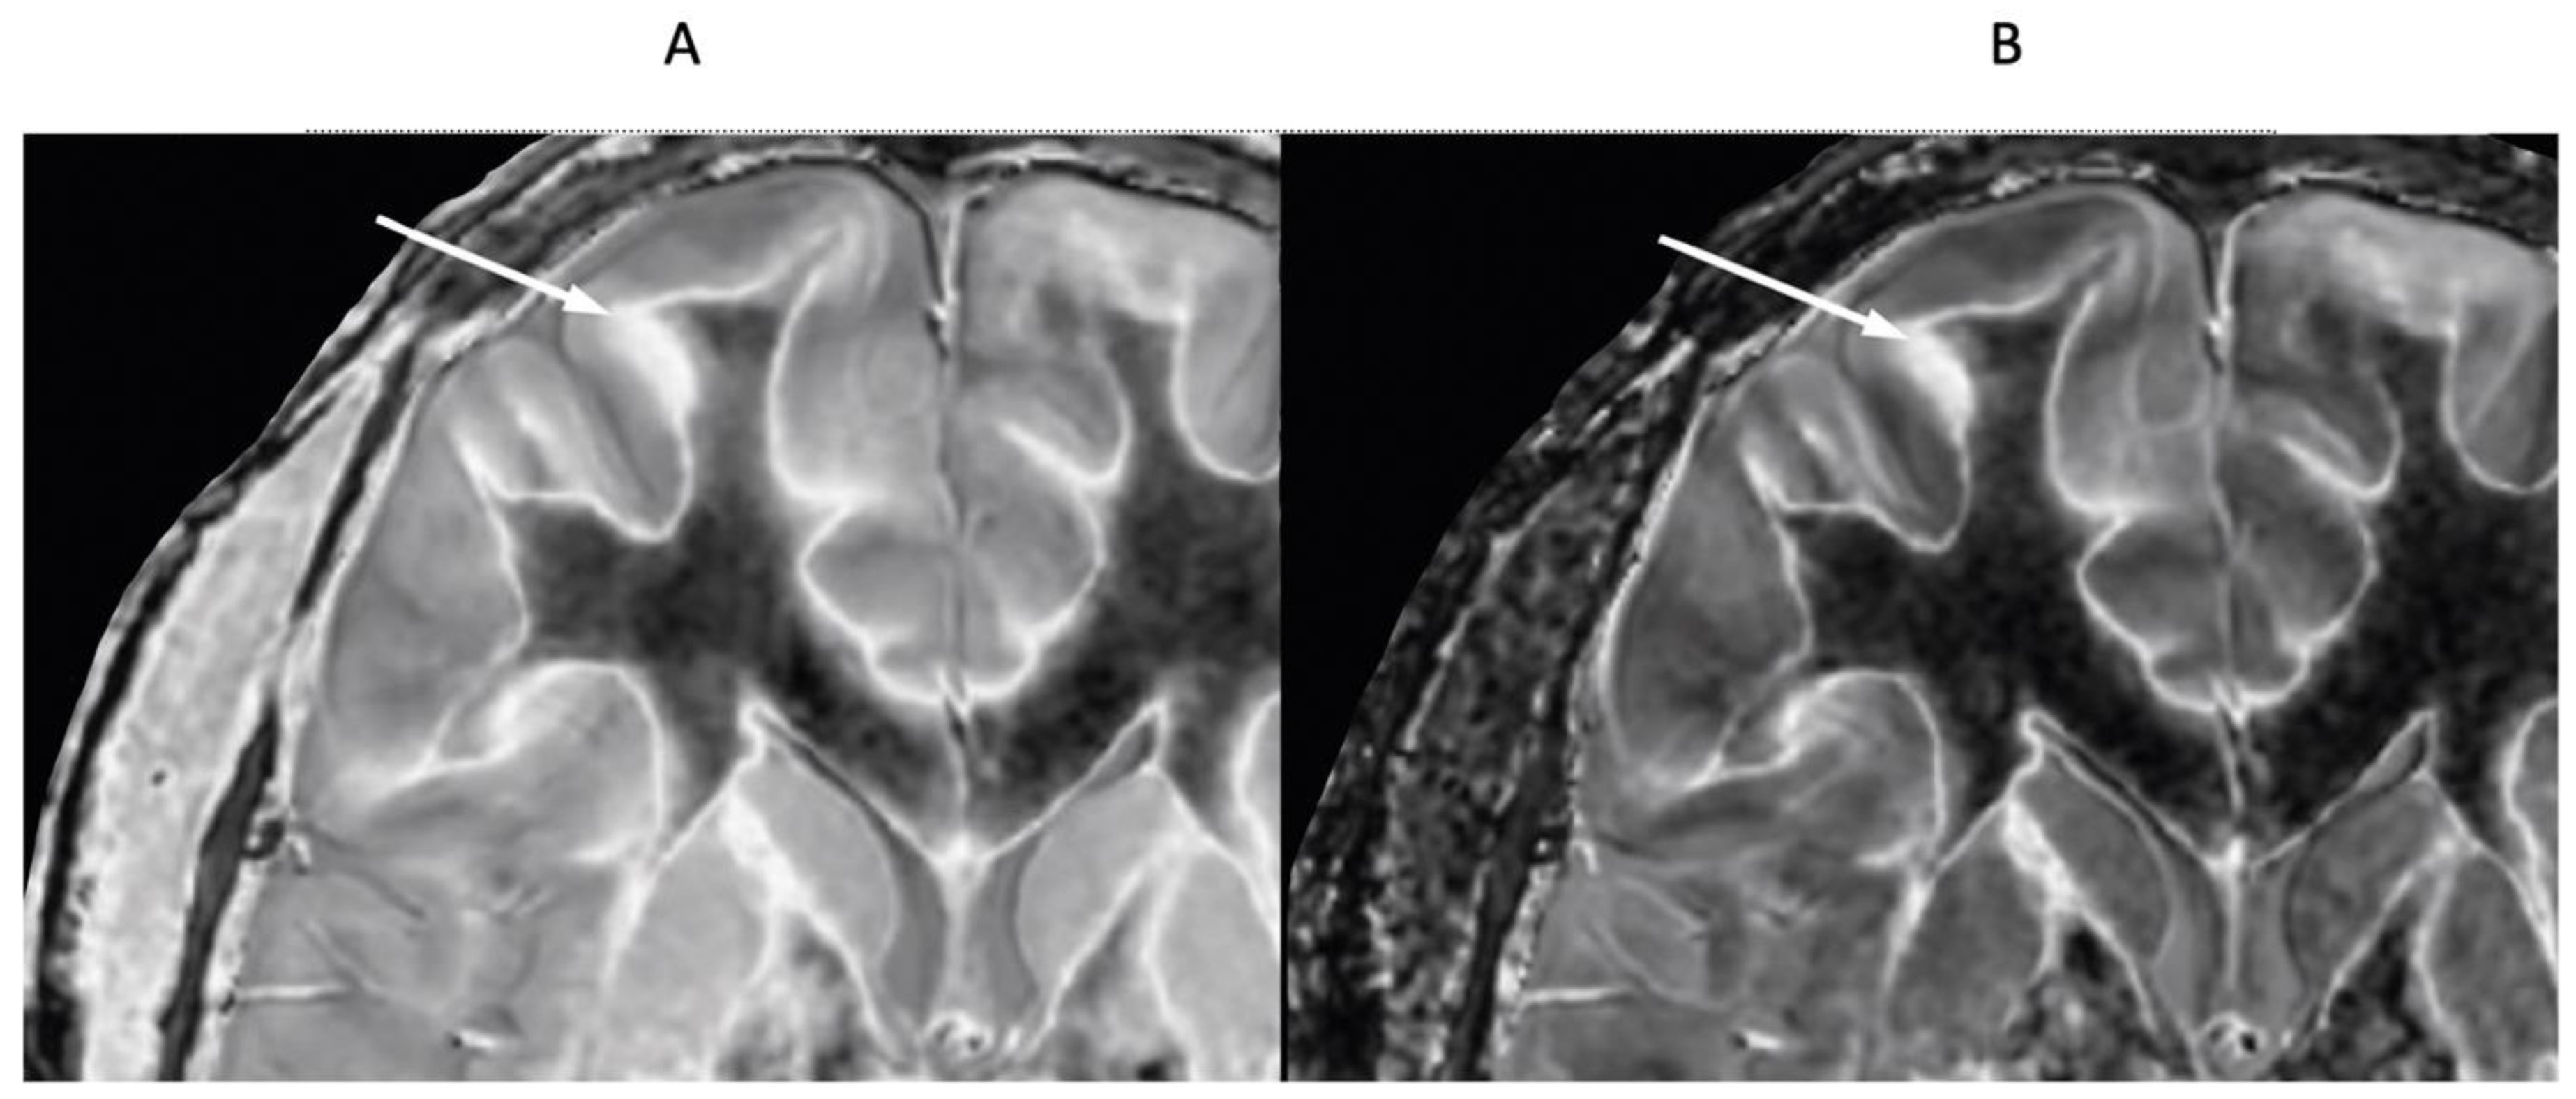

Normal Control and MS Patient with dSIR and lSIR Images

dSIR and lSIR images (

Figure 22A,B) are compared in a 46-year-old male normal control. White matter-gray matter boundaries and the bilaminar cortex sign (arrows) are seen with higher contrast and higher spatial resolution on the lSIR image. Bubble signs are also better seen in the thalamus and putamen on the lSIR image. A small decrease in T

1 through the sharp peak of the lSIR bipolar T

1-filter results in finer boundaries and narrower margin bubble signs with the lSIR bipolar T

1-filter compared to the dSIR bipolar T

1-filter.

In a 41-year-old female patient with MS, the dSIR image (

Figure 23A) shows a blurred leukocortical lesion in the right medial frontal region with no evidence of a white matter-gray matter boundary within it. The matched lSIR image (

Figure 23B) shows a disrupted high signal boundary between white matter and gray matter within the lesion. Profiles (plots of signal against position in mm) through the lesion at the level shown by the arrows for the dSIR (blue) and lSIR (orange) images shows a higher signal and steeper slope for the lSIR image (

Figure 23C). The spatial resolution of the contrast i.e., change in signal with change in position is generally higher on the lSIR image.

Figure 22.

46-year-old normal control. Narrow mD dSIR (A) and narrow mD lSIR (B) T1-BLAIR images with insets of anterior left cortex dSIR in (C) and anterior left cortex lSIR in (D). The boundaries between white matter and gray matter are seen with higher contrast and the contrast is seen with higher spatial resolution in (B) and (D) compared with (A) and (C). Bilaminar cortex signs are also seen with higher contrast and spatial resolution in (B) and (D) (white arrows). There are also small bubble signs in the putamen and medial thalamus which are better seen on the lSIR image (B) compared with the dSIR image (A).

Figure 23.

41-year-old female patient with MS. A leukocortical lesion in the right medial frontal region is shown on the narrow mD dSIR (T1-BLAIR) image (A) and a matching lSIR image (B) (arrows). There are also left to right profiles with signal plotted against position (in mm) for the dSIR (blue) and lSIR (orange) images (C) at the level of the horizontal arrows shown in (A) and (B). No boundary between white matter and gray matter is seen within the lesion in (A). A disrupted high signal boundary between white matter and gray matter is seen in the lesion in (B). The lSIR profile (orange) has higher signal and steeper slopes than the dSIR profile (blue) in (C). The difference in signal (or contrast) achieved for the same change in position is generally greater with the lSIR filter i.e., the contrast shown on the lSIR image generally has a higher spatial resolution.